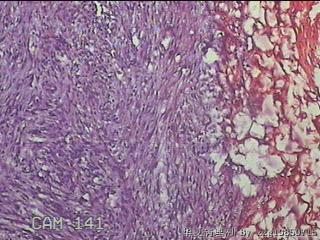

左肘部包块

性别

男

年龄

39

临床诊断

左肘部肿物:炎性脂肪瘤

一般病史

发现左肘部肿物1周。

标本名称

大体所见

灰白粉红色组织2x1.8x0.3㎝一团,表面结节状,光滑,切面灰白粉红色,质软。

图1